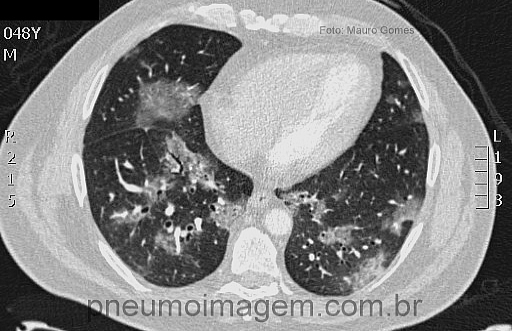

Veja imagens de pneumonia por vírus no PneumoImagem,

clicando aqui.